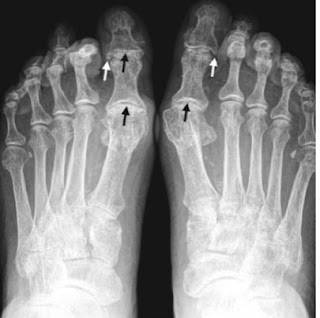

Las figuras 1, 2 y 3 ilustran ejemplos de signo, hallazgo y patrón.

Signo de la C2 ancha. Consiste en un aumento de la distancia entre el margen anterior y el posterior de C2 en relación con C3. Corresponde a una fractura oblicuad el cuerpo vertebral con desplazamiento de un fragmento obre el otro, dando la apariencia de una granda miento del diámetro anteroposterior. Según la oblicuidad de la línea de fractura, ésta puede no verse en la radiografía.